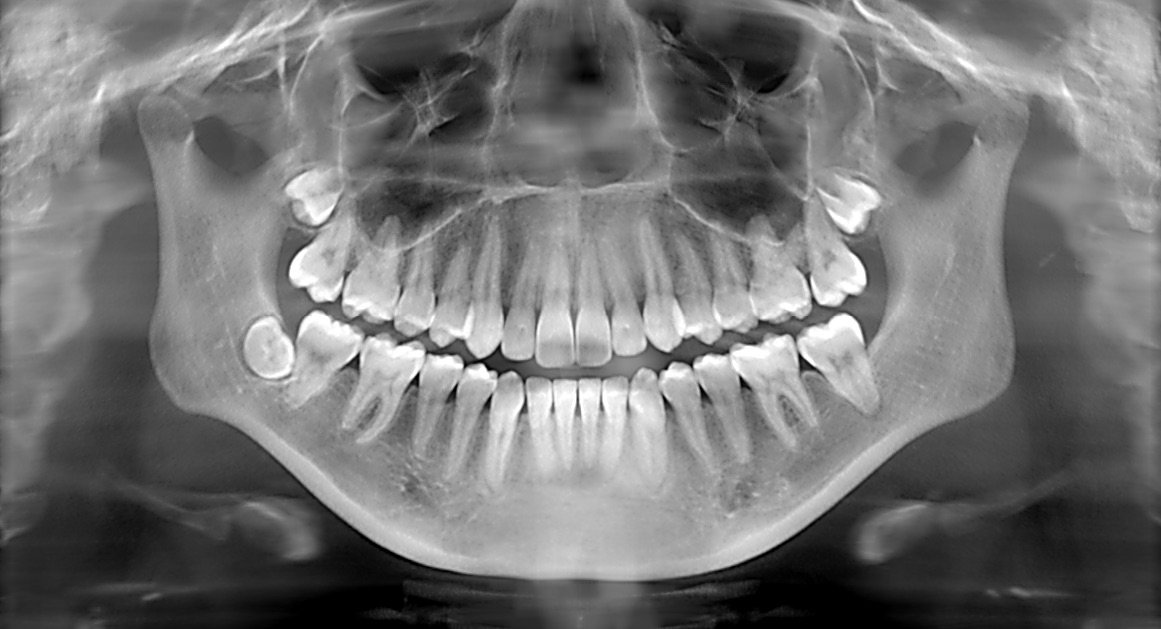

Enter precision diagnostics with dental X-rays. These modern diagnostic tools offer a non-invasive, comprehensive view of the mouth, allowing dentists to detect issues long before they manifest as painful symptoms. For Shweta, this meant peace of mind and a clear path to a healthier smile.

Precision diagnostics with dental X-rays represent a significant advancement in dental care. They offer a practical solution to a pervasive problem, allowing patients like Shweta to overcome their fears and take charge of their oral health. The clarity and precision provided by these X-rays can identify issues ranging from cavities and impacted teeth to bone loss and tumors, all without invasive procedures.